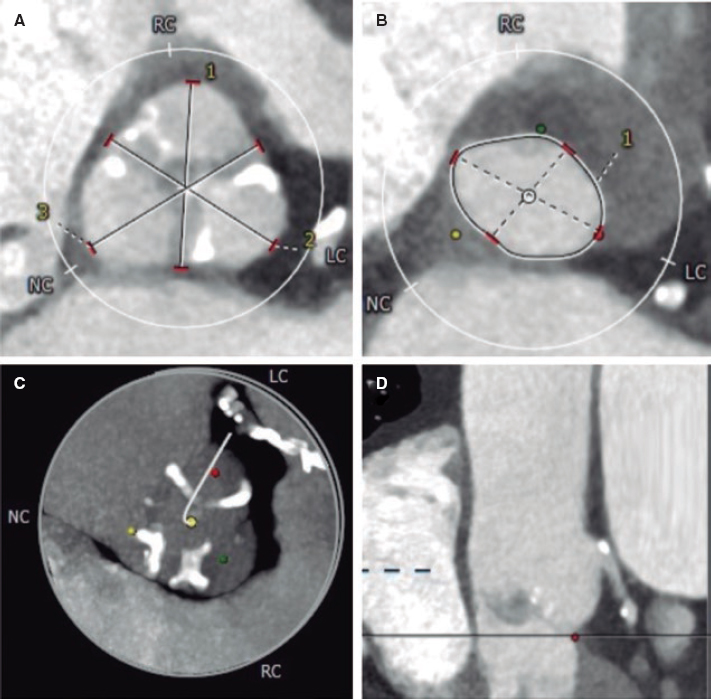

The magnetic resonance imaging study was conducted using a Signa HDx 3.0 T GE MR system through FIESTA balanced steady-state free precision multifarious sequences of specific cardiac planes (of 2, 3, and 4 chambers, and in the short axis) to assess both the anatomy and the cardiac function. All images were processed using the ReportCard 4.0 software package.

The 8-week follow-up revealed segmental alterations of contractility, lateral wall thinning, and fat transformation at posterior level in pig #1 and at posteroinferior level in pig #2 (figure 1). Ventricular volumes grew 10% and 7%, respectively.

Figure 1. Magnetic resonance imaging of animal #2. Short axis of the left ventricle. Presence of fat transformation at posterior level.